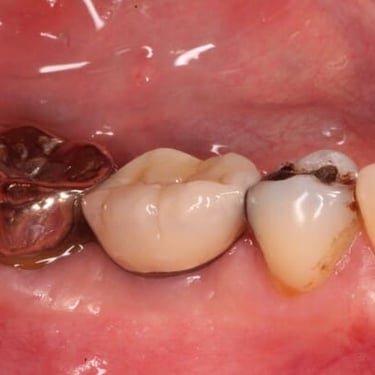

Implantes dentales fracasados

Los implantes dentales fracasados son aquellos que no se han integrado correctamente con el hueso o han desarrollado complicaciones postoperatorias.

Los pacientes pueden notar movilidad en el implante, dolor o inflamación.

El tratamiento puede incluir la extracción del implante fallido y la preparación para un nuevo implante.